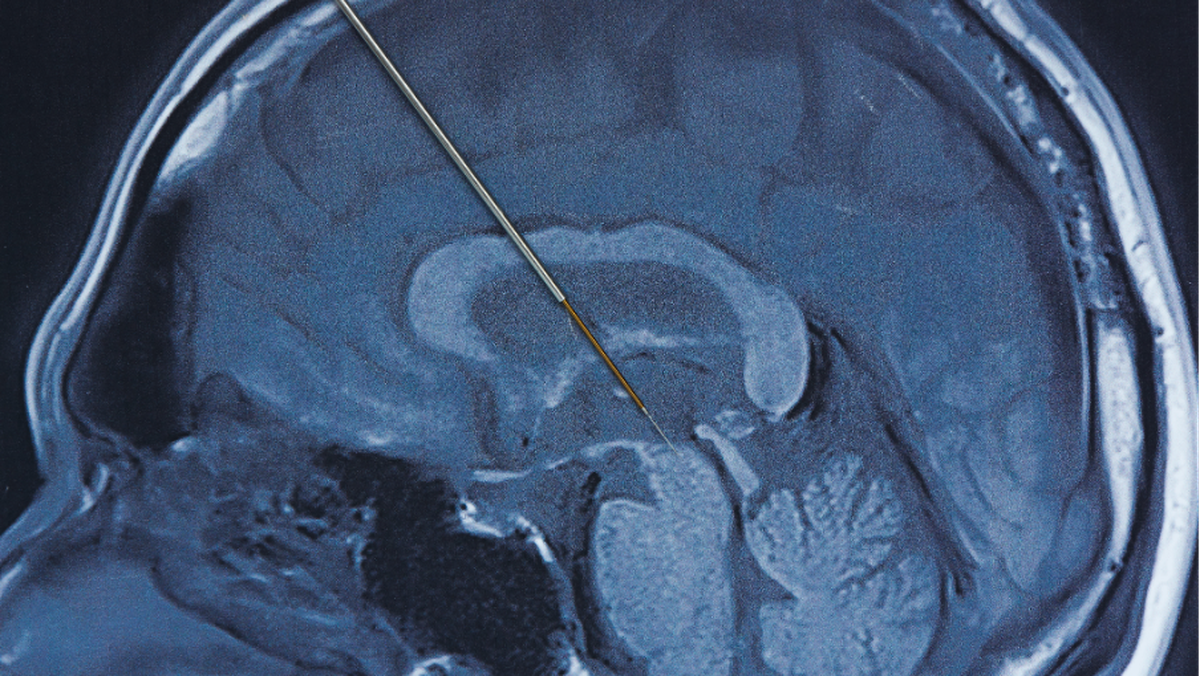

Deep brain stimulation merupakan prosedur bedah saraf yang melibatkan pemasangan elektroda Hingga area tertentu otak Sebagai Memberi rangsangan listrik terkontrol. Stimulasi ini bertujuan mengatur kembali sinyal saraf yang terganggu akibat Penyakit Parkinson.

Praktisi Medis spesialis saraf Hingga Siloam Hospitals Kebon Jeruk, dr. Frandy Susatia, Sp.S, RVT, menjelaskan bahwa elektroda tipis ditanam Hingga otak dan dihubungkan Hingga Alat stimulasi menyerupai alat pacu jantung. Alat ini dipasang Hingga bawah kulit dada Dibagian atas dan bekerja secara terus-menerus mengirimkan impuls listrik sesuai pengaturan Praktisi Medis.

Tahap pertama adalah pemasangan elektroda Hingga otak Bersama bius lokal agar pasien tetap sadar. Di tahap ini, Praktisi Medis dapat Menilai ketepatan lokasi elektroda Lewat simulasi yang diberikan, sambil pasien diminta Sebagai Memberi umpan balik Yang Terkait Bersama perubahan Tanda yang dirasakan. Sesudah lokasi dan jumlah stimulasi yang optimal ditemukan, proses pemasangan Alat DBS secara permanen Berencana dilakukan.

Tahap kedua dilakukan Bersama bius umum Sebagai menanam Alat stimulasi permanen Hingga bawah kulit dada Dibagian atas. Elektroda Hingga otak Lalu dihubungkan Hingga Alat tersebut Lewat kabel halus yang dipasang Hingga bawah kulit.